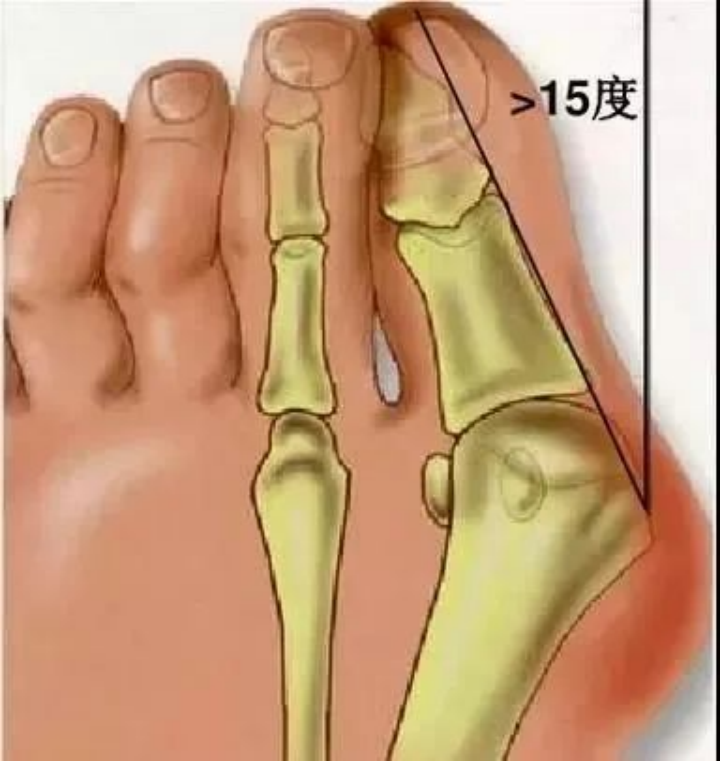

如何判断自己是否有拇外翻?

正常人足的第一足趾轴线,与足的第一跖骨轴线,两者之间的夹角在0~15度之间。如果超过15度,就是拇外翻了。